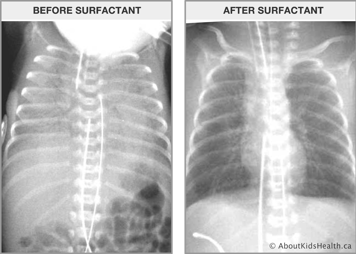

Surfactant replacement therapy

Surfactant is available as a medication to treat babies with RDS. It is a liquid that is derived from animals or is synthetically produced and can be administered into a baby’s lungs. There are several different methods that are used to administer surfactant. Depending on the severity of the lung condition, surfactant may be administered more than once.

Extremely premature babies who have RDS and require mechanical ventilation will often be given surfactant replacement prior to transfer to another hospital.